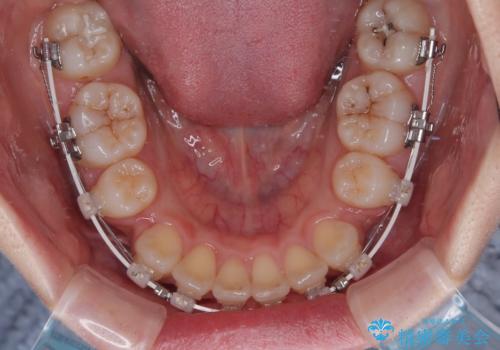

- 矯正装置

- 審美装置

- 上顎前歯の突出感を気にして来院された患者様です。

上下左右第一小臼歯4本を抜歯して、積極的に口元を引っ込めるよう、ワイヤー装置にて矯正治療を行うこととしました。